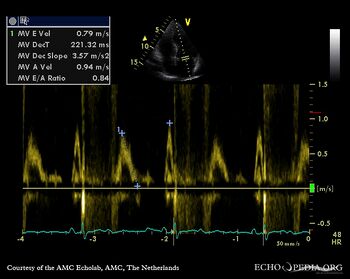

| Pulsed-wave Doppler signal of mitral inflow: impaired relaxation | Pulsed-wave Doppler signal of pulmonary venous flow |